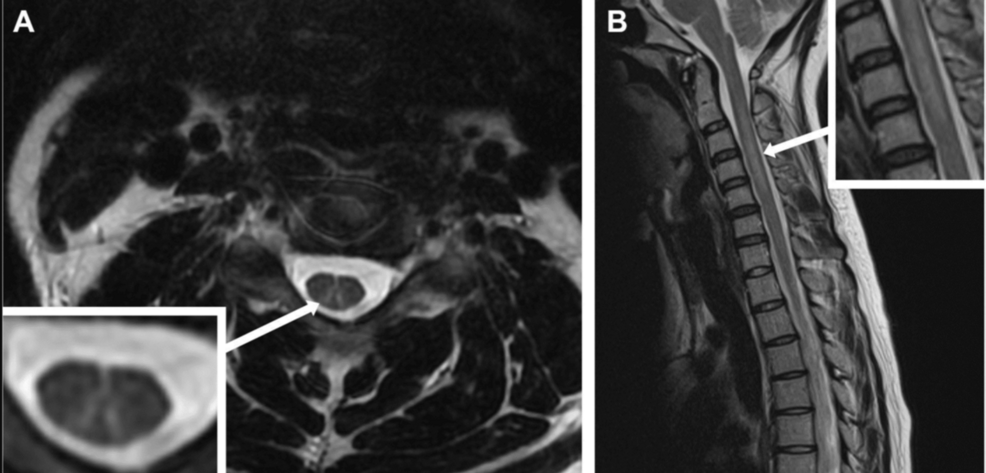

Magnetic resonance imaging (MRI) of the spinal cord typically shows T2 hyperintensities in the dorsal columns, especially in the cervical and upper thoracic regions, consistent with SCD (Figure 2) [8]. Nerve conduction studies may show axonal or demyelinating features.